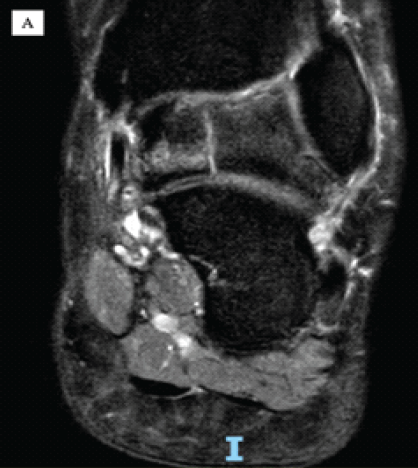

Letter to the Editor: Revisiting the “Ice Cream Scoop” Sign in Adult Elbow Tuberculosis: Extending Beyond the Pediatric Population

Nadeem Akhtar Qureshi

………………………………p.555-556